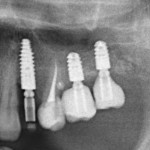

Для этого мы сделали КЛКТ:

И КЛКТ показала нам, что с имплантатами и окружающей костью всё зашибись. Через 12 лет после операции, отсутствия наблюдения, пофигизма в замене временных коронок! Нужны ли тебе еще какие-нибудь доводы в пользу долгосрочной эффективности метода?

Серия контрольных снимков на этапах:

Вот так закончилась 12-летняя эпопея Зинаиды с восстановлением зубов на нижней челюсти. Через пару дней она уехала на экскурсию в Санкт-Петербург (на всякий случай, мы попросили задержаться в России, вдруг потребуется коррекция), а оттуда — домой, в дружественную страну. Судя по тому, что она нам пишет — у неё всё прекрасно и хорошо. Зинаида обещает не пропускать профилактические осмотры и наблюдаться у стоматолога по месту жительства.